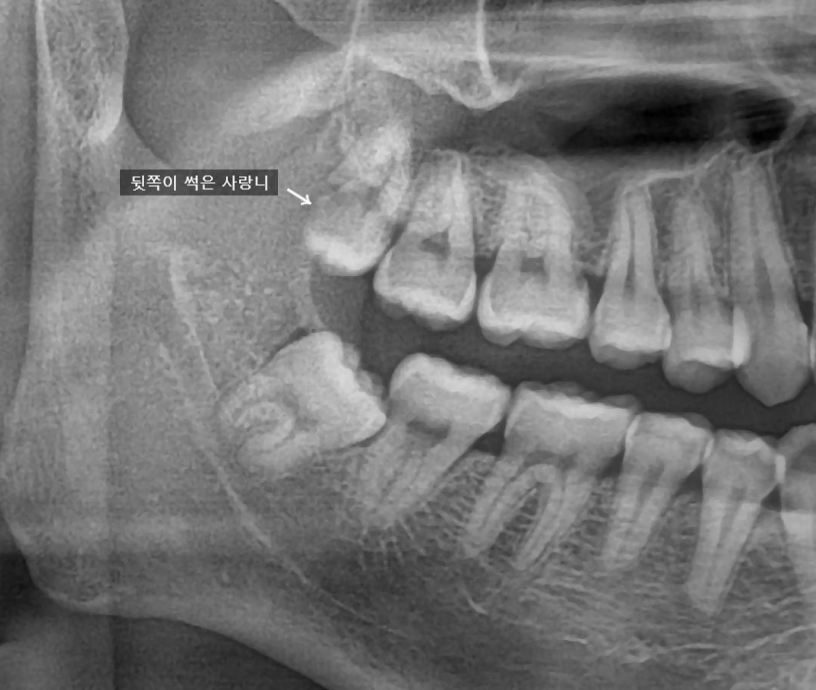

특히 이렇게 가장 뒷쪽에 난 사랑니의 경우

양치질이 제대로 되지 않는 경우가 많아서

쉽게 썩게됩니다.

썩은 걸 제가 봤다 하면은

그냥 둘 수가 없어요

꼭 뽑자고 말씀을 드립니다.